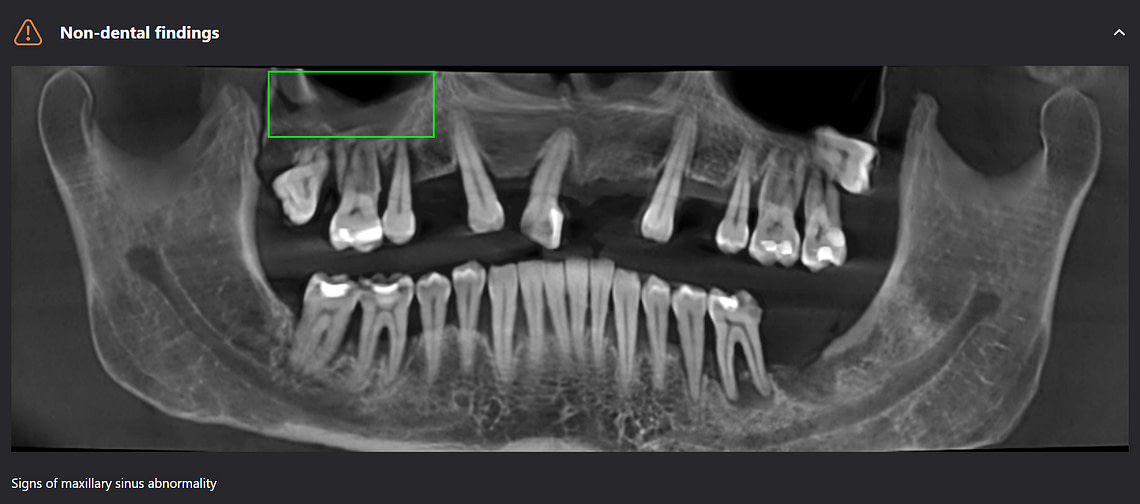

Diagnocat can pick up non-dental pathology as well, such as thickening of the sinus lining and bone cysts.

Panoramic radiological report

CBCT radiological report